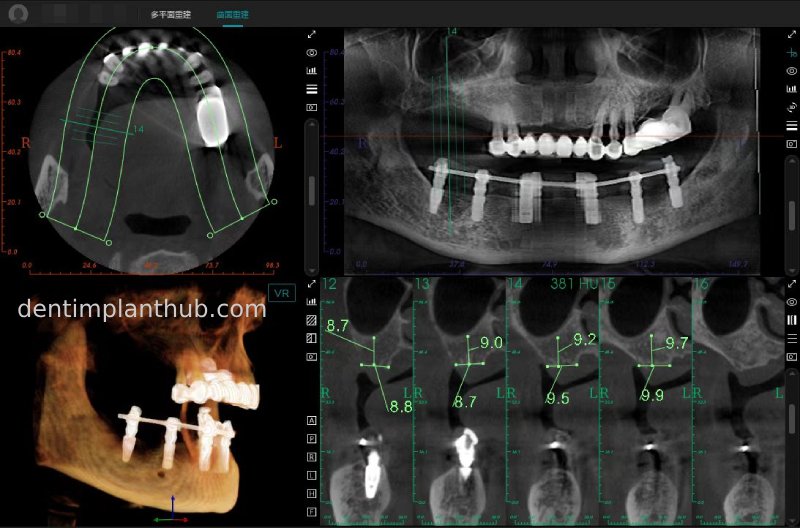

A review of the CBCT on 6/10/23 was more promising and a surgical plan was subsequently drawn up.

General schematic of the surgical programme

Detailed list of implant types and composite abutments to be prepared.

46 tooth position, implant model number 4810, RC series straight composite abutment;

44 tooth position, implant model number 4110, RC series straight composite abutment;

42 tooth position, implant model number 4110, RC series straight composite abutment; alternate implant model number 3310, alternate NC series straight composite abutment;

32 tooth position, implant model number 4110, RC series straight composite abutment; alternate implant model number 3310,. Alternate NC Series Straight Composite Abutment;

34 Dental Position, Implant Model No. 4110, RC Series Straight Composite Abutment;

36 Dental Position, Implant Model No. 4808, RC Series Straight Composite Abutment;